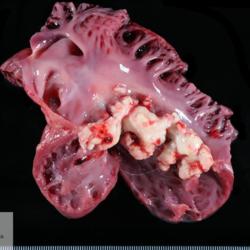

Pàgina anterior de 637 Pàgina següent 3181 total Porcine Specie: Porcine Organ: Heart Lesion: Endocarditis Lesion modifier: Endocarditis - Valvular Disease: - Position: 33 (7 views) Porcine Specie: Porcine Organ: Heart Lesion: Endocarditis Lesion modifier: Endocarditis - Valvular Disease: - Not viewed Canine Specie: Canine Organ: Intestine Lesion: Obstruction Lesion modifier: - Disease: - Files/Expedient: N-165/15 Position: 252 (1 views) Feline Specie: Feline Organ: Lung Lesion: Carcinoma Lesion modifier: Carcinoma - Adenocarcinoma Disease: - Files/Expedient: N-161/15 Position: 136 (2 views) Canine Specie: Canine Organ: Thoracic cavity Lesion: Atelectasis Lesion modifier: - Disease: - Files/Expedient: N-160/15 Not viewed Pàgina anterior de 637 Pàgina següent Títol Select...Avian (Exotic) (110)Avian (Poultry) (76)Bovine (317)Canine (935)Caprine (47)Equine (257)Feline (326)Ferret (19)General (127)Marine mammal (22)Non-human primate (20)Ovine (328)Porcine (379)Rabbit (61)Reptile (38)Rodent (28)Wildlife (91) Format Select...- (60)Abomasum (37)Adrenal gland (10)Blood (7)Blood vessel (50)Body as a whole (19)Bone (57)Bone marrow (21)Brain (93)Cloaca (1)Diaphragm (2)Ear (5)Esophagus (39)Eye (16)Fetus (12)Gallbladder (23)Gizzard (2)Heart (265)Intestine (356)Joint (32)Kidney (443)Larynx (5)Liver (326)Lung (264)Lymph node (91)Mammary gland (10)Mediastinum (1)Muscle (22)Nasal cavity (22)Nerve (7)Omasum (5)Oral cavity (63)Ovary (14)Oviduct (8)Pancreas (7)Parathyroid (5)Penis (10)Peritoneum (65)Pharynx (9)Pituitary gland (6)Placenta (7)Prostate (8)Proventriculus (3)Reticulum (1)Rumen (28)Sinus (7)Skin (181)Spinal cord (15)Spleen (105)Stomach (125)Teeth (1)Testicle (11)Thoracic cavity (31)Thymus (13)Thyroid gland (5)Tongue (32)Tonsils (11)Trachea (11)Urethra (5)Urinay bladder (61)Uterus (27)Vagina (1)Vulva (1)Yolk sac (1) Cobertura Select...- (152)Abomasitis (26)Abscess (27)Acidosis (1)Adenocarcinoma (20)Adenoma (9)Aerosacculitis (6)Agenesis (1)Agnathia (1)Alopecia (7)Amyloidosis (12)Aneurysm (6)Angiectasis (1)Anthracosis (1)Arteritis (11)Arthritis (15)Arthrogryposis (6)Artifact (4)Ascites (13)Atelectasis (8)Atherosclerosis (5)Atresia (1)Atrial septal defect (2)Atrophy (10)Autolysis (7)Bronchitis (6)Bronchopneumonia (26)Cachexia (2)Carcinoma (103)Cardiomyopathy (19)Cellulitis (2)Chemodectoma (4)Cholangiohepatitis (4)Cholangitis (19)Cholecystitis (4)Cholestasis (5)Chondrodysplasia (2)Chondrosarcoma (2)Chronic passive congestion (13)Chylothorax (2)Cirrhosis (6)Coelomitis (3)Coenurus cerebralis (4)Colitis (40)Congestion (17)Conjunctivitis (5)Coronitis (3)Cryptorchidism (3)Cyst (25)Cystitis (24)Dermatitis (69)Diaphragmatic hernia (4)Dilation (28)Discospondylitis (1)Disseminated intravascular coagulation (7)Dyschondroplasia (1)Dysplasia (29)Ectopia cordis (1)Ectopic ureter (1)Edema (55)Emphysema (5)Encephalitis (5)Endocardiosis (14)Endocarditis (26)Endometritis (5)Enteritis (118)Enterolith (6)Epulis (3)Esophagitis (14)Fasciitis (1)Fibrosis (7)Fibrous osteodystrophy (8)Fistula (1)Folliculitis (3)Fracture (2)Gastritis (34)Gingivitis (5)Glioma (8)Glomerulonephritis (21)Glossitis (25)Glycogenosis (1)Gout (8)Granuloma (2)Granulosa cell tumor (4)Hemangioma (9)Hemangiosarcoma (46)Hematoma (8)Hemoglobinuria (2)Hemopericardium (12)Hemoperitoneum (2)Hemorrhage (100)Hemosiderosis (7)Hemothorax (2)Hepatitis (78)Hernia (11)Histiocytosis (3)Hydatid cyst (11)Hydrocephalus (9)Hydrometra (1)Hydronephrosis (22)Hydropericardium (6)Hydrothorax (3)Hydroureter (5)Hyperkeratosis (8)Hyperostosis (4)Hyperplasia (37)Hypertrophy (9)Hypopigmentation (1)Hypoplasia (7)Hypopyon (1)Impaction (6)Infarction (63)Insulinoma (6)Intussusception (5)Jaundice (17)Laminitis (2)Laryngitis (2)Leiomyoma (5)Leukemia (13)Lipidosis (36)Lipoma (7)Lymphadenitis (45)Lymphadenopathy (7)Lymphangiectasia (6)Lymphangitis (5)Lymphoma (221)Malacia (11)Malignant melanoma (15)Mast cell tumor (11)Mastitis (8)Megaesophagus (2)Melanosis (3)Melena (4)Meningioma (6)Meningitis (6)Meningocele (2)Meningoencephalitis (5)Mesothelioma (5)Methemoglobinemia (2)Mineralization (10)Mucocele (5)Mucometra (1)Multilobular bone tumor (1)Mummification (3)Myelofibrosis (1)Myocarditis (4)Myositis (5)Necrosis (81)Nephritis (113)Nephroblastoma (6)Nephrosclerosis (1)Nephrosis (14)Neuritis (1)Obstruction (13)Omasitis (4)Omphalitis (1)Omphalophlebitis (7)Orchitis (4)Osteoarthrosis (5)Osteomyelitis (9)Otitis (2)Palatoschisis (3)Pancreatitis (3)Panniculitis (3)Papilloma (7)Parakeratosis (14)Patent ductus arteriosus (6)Peliosis hepatis (1)Perforation (17)Pericarditis (35)Peritonitis (39)Persistent right aortic arch (1)Pharyngitis (2)Pheochromocytoma (2)Phlebitis (2)Placentitis (6)Pleuritis (21)Pleuropneumonia (24)Pneumonia (109)Pneumothorax (3)Polycystosis (14)Polyp (5)Polyserositis (6)Posthitis (1)Proctitis (4)Prolapse (3)Prostatitis (3)Proventriculitis (1)Pyelonephritis (24)Pyometra (6)Pyothorax (4)Rhinitis (11)Rumenitis (6)Rupture (24)Salpingitis (3)Sarcoma (57)Sclerosis (1)Scoliosis (2)Seminoma (2)Sequestrum (2)Serous atrophy (14)Sinusitis (7)Splenitis (14)Splenomegaly (9)Spondylitis (6)Spondylosis (1)Stenosis (9)Stomatitis (32)Tenosynovitis (2)Teratoma (3)Thricobezoar (2)Thrombosis (16)Tonsilitis (4)Torsion (13)Tracheitis (4)Tympany (7)Typhlitis (8)Typhlocolitis (4)Ulcer (43)Urethritis (1)Urolithiasis (36)Uroperitoneum (1)Uveitis (1)Vasculitis (15)Ventricular septal defect (3)Volvulus (11) Matèria Select... - (14)- (1653)- (152)Abomasitis - Catarrhal (2)Abomasitis - Catarrhal-hemorrhagic (1)Abomasitis - Chronic (1)Abomasitis - Fibrinous-necrotizing (2)Abomasitis - Hyperplasic (5)Abomasitis - Hyperplasic - Chronic (1)Abomasitis - Necrotic (1)Abomasitis - Necrotizing (2)Abomasitis - Ulcerative (5)Adenocarcinoma (9)Aerosacculitis - Granulomatous (1)Amyloidosis - Chronic (1)Arteritis - Necrotic (2)Arteritis - Necrotizing (1)Arthritis - Chronic (4)Arthritis - Fibrinous-purulent (3)Arthritis - Serous (4)Arthritis - Subacute (1)Ascites - Serous (1)Atrophy - Serous (1)Bronchitis - Catarrhal (3)Bronchitis - Suppurative (1)Bronchopneumonia - Catarrhal-purulent (17)Bronchopneumonia - Fibrinous (1)Bronchopneumonia - Granulomatous (1)Bronchopneumonia - Purulent (1)Bronchopneumonia - Suppurative (5)Carcinoma - Adenocarcinoma (33)Carcinoma - Adenocarcinoma - Hepatocellular (2)Carcinoma - Adenocarcinoma - Mucinous (1)Carcinoma - Basosquamous (1)Carcinoma - Cholangiocellular (3)Carcinoma - Hepatocellular (4)Carcinoma - Metastatic (3)Carcinoma - Squamous cell carcinoma (13)Carcinoma - Transitional cell (2)Cardiomyopathy - Dilated (13)Cardiomyopathy - Hypertrophic (6)Cellulitis - Necrotizing (1)Cholangitis - Chronic (8)Cholangitis - Hyperplasic (3)Cholecystitis - Fibrinous-necrotizing (1)Coelomitis - Fibrinous (1)Coelomitis - Granulomatous (1)Colitis - Catarrhal (3)Colitis - Catarrhal-hemorrhagic (1)Colitis - Fibrinous (1)Colitis - Fibrinous-necrotizing (1)Colitis - Fibrinous-necrotizing (Diphtheritic) (6)Colitis - Granulomatous (2)Colitis - Hemorrhagic (4)Colitis - Hemorrhagic-necrotizing (3)Colitis - Necrotizing (2)Colitis - Ulcerative (6)Congestion - Chronic (2)Conjunctivitis - Hyperplasic (1)Conjunctivitis - Purulent (3)Coronitis - Ulcerative (1)Cystitis - Chronic (3)Cystitis - Fibrinous (1)Cystitis - Fibrinous-necrotizing (1)Cystitis - Follicular (1)Cystitis - Hemorrhagic (6)Cystitis - Hemorrhagic-ulcerative (1)Cystitis - Necrotizing (9)Cystitis - Perforated (1)Dermatitis - Granulomatous (14)Dermatitis - Hyperkeratotic (10)Dermatitis - Hyperplasic (proliferative) (1)Dermatitis - Hyperplastic (10)Dermatitis - Necrotizing (4)Dermatitis - Pustular (4)Dermatitis - Ulcerative (2)Dilation - Chronic (1)Discospondylitis - Necrotizing (1)Dysplasia - Follicular (5)Edema - Interstitial (6)Emphysema - Interstitial (1)Encephalitis - Granulomatous (1)Encephalitis - Nonsuppurative (1)Endocardiosis - Mitral (7)Endocardiosis - Mitral - Chronic (5)Endocarditis - Valvular (6)Endocarditis - Valvular - Mitral (7)Endocarditis - Valvular - Pulmonic (1)Endocarditis - Valvular - Subacute (1)Endocarditis - Valvular - Subaortic (5)Endocarditis - Valvular - Tricuspid (4)Endometritis - Purulent (3)Endometritis - Purulent-hemorrhagic (2)Enteritis - Catarrhal (23)Enteritis - Catarrhal - Acute (1)Enteritis - Catarrhal-hemorrhagic (5)Enteritis - Catarrhal-hemorrhagic - Acute (2)Enteritis - Fibrinous (16)Enteritis - Fibrinous - Acute (3)Enteritis - Fibrinous-necrotizing (7)Enteritis - Granulomatous (14)Enteritis - Granulomatous - Chronic (1)Enteritis - Granulomatous - Multifocal (1)Enteritis - Hemorrhagic (17)Enteritis - Hemorrhagic - Acute (1)Enteritis - Hemorrhagic-necrotizing (1)Enteritis - Hyperplasic (proliferative) (4)Enteritis - Necrotizing (4)Enteritis - Necrotizing - Acute (1)Enteritis - Necrotizing - Hemorrhagic (1)Enteritis - Necrotizing-ulcerative (2)Enteritis - Ulcerative (1)Enteritis - Ulcerative-hemorrhagic (1)Esophagitis - Erosive-ulcerative (6)Esophagitis - Necrotizing (4)Esophagitis - Ulcerative (1)Esophagitis - Ulcerative-necrotizing (1)Fasciitis - Fibrinous-purulent (1)Folliculitis - Purulent (2)Gastritis - Catarrhal (2)Gastritis - Chronic (1)Gastritis - Follicular (1)Gastritis - Hemorrhagic (2)Gastritis - Hemorrhagic-necrotizing (1)Gastritis - Hypertrophic (2)Gastritis - Inclusion bodies (1)Gastritis - Mineralization (1)Gastritis - Mycotic (1)Gastritis - Necrotizing (2)Gastritis - Ulcerative (6)Gastritis - Uremic (3)Gingivitis - Erosive (2)Gingivitis - Hyperplasic (proliferative) (1)Gingivitis - Necrotizing (1)Glomerulonephritis - Chronic (7)Glomerulonephritis - Membranoproliferative (3)Glomerulonephritis - Membranoproliferative - Chronic (1)Glomerulonephritis - Membranous (3)Glomerulonephritis - Membranous - Chronic (1)Glomerulonephritis - Proliferative (2)Glomerulonephritis - Subacute (1)Glossitis - Erosive (2)Glossitis - Granulomatous (6)Glossitis - Hyperplasic (1)Glossitis - Hyperplasic (proliferative) (2)Glossitis - Hyperplastic (1)Glossitis - Necrotizing (2)Glossitis - Necrotizing - Focal (1)Glossitis - Ulcerative (6)Glossitis - Ulcerative - Multifocal (1)Glossitis - Ulcerative - Subacute (1)Glycogenosis (1)Granuloma - Eosinophilic (1)Hemangiosarcoma - Metastatic (2)Hemorrhage - Acute (1)Hemorrhage - Subcapsular (3)Hepatitis - Abscess (9)Hepatitis - Acute (3)Hepatitis - Chronic (4)Hepatitis - Chronic interstitial (6)Hepatitis - Granulomatous (7)Hepatitis - Interstitial - Multifocal (1)Hepatitis - Interstitial - Subacute (1)Hepatitis - Necrotizing (17)Hepatitis - Necrotizing - Acute (2)Hepatitis - Necrotizing - Hemorrhagic (1)Hepatitis - Necrotizing - Subacute (1)Hepatitis - Pyogranulomatous (7)Hepatitis - Subacute (4)Hydronephrosis - Chronic (1)Hydropericardium - Chronic (1)Hyperplasia - Erythroid (1)Hyperplasia - Lymphoid (3)Hyperplasia - Myeloid (1)Hyperplasia - Nodular (8)Hypertrophy - Concentric (2)Hypertrophy - Eccentric (3)Infarction - Acute (17)Infarction - Acute - Multifocal (2)Infarction - Chronic (5)Infarction - Chronic - Multifocal (1)Infarction - Subacute (18)Infarction - Subacute - Focal (2)Laminitis - Chronic (2)Laryngitis - Necrotic (1)Laryngitis - Necrotizing (1)Leukemia - Lymphoid leukemia (2)Leukemia - Non-lymphoid leukemia (6)Lipidosis - Multifocal (1)Lipidosis - Panlobular (1)Lipidosis - Panlobular - Generalized (2)Lymphadenitis - Granulomatous (24)Lymphadenitis - Granulomatous - Chronic (3)Lymphadenitis - Hemorrhagic (1)Lymphadenitis - Necrotizing (5)Lymphadenitis - Necrotizing (caseous) (11)Lymphangitis - Granulomatous (1)Lymphangitis - Purulent (1)Lymphangitis - Ulcerative (1)Lymphoma - Alimentary lymphoma (7)Lymphoma - Cutaneous lymphoma (6)Lymphoma - Lymphosarcoma (2)Lymphoma - Mediastinal lymphoma (1)Lymphoma - Multicentric lymphoma (29)Malignant melanoma - Malignant (1)Malignant melanoma - Metastatic (1)Mast cell tumor - Metastatic (1)Mastitis - Fibrinous-purulent (2)Mastitis - Necrotic (1)Mastitis - Purulent (3)Mastitis - Suppurative (1)Meningitis - Fibrinous-purulent (2)Meningitis - Purulent (4)Meningoencephalitis - Necrotizing (3)Meningoencephalitis - Nonsuppurative (2)Mineralization - Metastatic (4)Myocarditis - Fibrous - Chronic (1)Myocarditis - Granulomatous (1)Myositis - Purulent (2)Necrosis - Acute (1)Necrosis - Cortical (5)Necrosis - Follicular (1)Necrosis - Papillary (8)Necrosis - Papillary - Acute (3)Necrosis - Subacute (3)Necrosis - Tubular (6)Nephritis - Embolic (2)Nephritis - Embolic suppurative (7)Nephritis - Granulomatous (27)Nephritis - Granulomatous - Chronic (1)Nephritis - Granulomatous - Multifocal (1)Nephritis - Interstitial (6)Nephritis - Interstitial - Acute (4)Nephritis - Interstitial - Chronic (41)Nephritis - Interstitial - Subacute (12)Nephritis - Purulent (7)Nephritis - Purulent - Acute (2)Nephritis - Purulent - Multifocal (3)Nephrosis - Cholemic (3)Nephrosis - Hemoglobinuric (10)Omasitis - Fibrinous-necrotizing (1)Omasitis - Hyperkeratotic (1)Omasitis - Necrotizing (2)Omphalophlebitis - Fibrinous-purulent (2)Omphalophlebitis - Purulent (3)Orchitis - Necrotizing (1)Osteomyelitis - Necrotizing (7)Osteomyelitis - Purulent (2)Otitis - Necrotizing (1)Otitis - Proliferative (1)Pancreatitis - Acute (1)Pancreatitis - Chronic (1)Pancreatitis - Granulomatous (1)Panniculitis - Fibrinous-purulent (1)Panniculitis - Necrotic (1)Panniculitis - Parasitic (1)Perforation - Acute (2)Pericarditis - Fibrinous (19)Pericarditis - Fibrinous - Subacute (1)Pericarditis - Fibrinous-necrotizing (1)Pericarditis - Fibrinous-purulent (3)Pericarditis - Fibrous (1)Pericarditis - Fibrous - Chronic (1)Pericarditis - Gangrenous (6)Pericarditis - Granulomatous (1)Pericarditis - Granulomatous - Chronic (2)Peritonitis - Acute (1)Peritonitis - Fibrinous (11)Peritonitis - Fibrinous - Subacute (1)Peritonitis - Fibrinous-purulent (5)Peritonitis - Fibrous (3)Peritonitis - Granulomatous (6)Peritonitis - Purulent (1)Peritonitis - Purulent-hemorrhagic (1)Peritonitis - Pyogranulomatous (3)Pharyngitis - Fibrinous-necrotizing (1)Pharyngitis - Ulcerative (1)Pheochromocytoma - Metastatic (1)Phlebitis - Purulent (1)Placentitis - Fibrinous-necrotizing (1)Placentitis - Necrotic (1)Placentitis - Necrotizing (1)Pleuritis - Chronic (1)Pleuritis - Fibrinous (3)Pleuritis - Fibrinous-purulent (2)Pleuritis - Fibrous (2)Pleuritis - Granulomatous (3)Pleuritis - Hyperplastic (2)Pleuritis - Purulent (2)Pleuritis - Pyogranulomatous (1)Pleuropneumonia - Fibrinous (13)Pleuropneumonia - Fibrinous-necrotizing (5)Pleuropneumonia - Granulomatous (2)Pleuropneumonia - Hemorrhagic-necrotizing (4)Pneumonia - Aspiration (11)Pneumonia - Bronchointerstitial (4)Pneumonia - Bronchointerstitial - Subacute (1)Pneumonia - Embolic (5)Pneumonia - Granulomatous (37)Pneumonia - Granulomatous - Multifocal (4)Pneumonia - Hemorrhagic-necrotizing (2)Pneumonia - Interstitial (7)Pneumonia - Interstitial - Acute (8)Pneumonia - Interstitial - Chronic (6)Pneumonia - Interstitial - Subacute (15)Pneumonia - Necrotizing (2)Pneumonia - Pyogranulomatous (2)Pneumonia - Verminous (5)Polyserositis - Fibrinous (6)Polyserositis - Fibrous (1)Proctitis - Fibrinous-necrotizing (1)Proctitis - Parasitic (2)Prostatitis - Purulent (1)Pyelonephritis - Acute (2)Pyelonephritis - Chronic (3)Rhinitis - Catarrhal (2)Rhinitis - Fibrinous (1)Rhinitis - Granulomatous (4)Rhinitis - Purulent (3)Rumenitis - Acute (1)Rumenitis - Erosive (1)Rumenitis - Necrotizing (1)Rupture - Acute (3)Sarcoma - Fibrosarcoma (12)Sarcoma - Hemangiosarcoma (11)Sarcoma - Histiocytic (7)Sarcoma - Metastatic (1)Sarcoma - Multilobular tumor of bone (1)Sequestrum - Chronic (2)Sinusitis - Suppurative (1)Splenitis - Granulomatous (8)Splenitis - Granulomatous - Chronic (1)Splenitis - Necrotizing (3)Splenitis - Necrotizing (caseous) (2)Spondylitis - Necrotizing (2)Stenosis - Intestinal (1)Stenosis - Valvular - Subaortic (4)Stomatitis - Erosive (12)Stomatitis - Erosive-ulcerative (3)Stomatitis - Fibrinous-necrotizing (1)Stomatitis - Fibrinous-necrotizing (Diphtheritic) (1)Stomatitis - Granulomatous (1)Stomatitis - Hyperplasic (1)Stomatitis - Hyperplasic (proliferative) (1)Stomatitis - Necrotizing (2)Stomatitis - Ulcerative (5)Stomatitis - Ulcerative - Multifocal (1)Stomatitis - Ulcerative-necrotizing (1)Tonsilitis - Necrotizing (4)Torsion - Acute passive hyperemia (5)Tracheitis - Catarrhal (3)Tracheitis - Fibrinous (1)Tracheitis - Granulomatous (1)Typhlitis - Catarrhal (1)Typhlitis - Fibrinous-necrotizing (2)Typhlitis - Hemorrhagic (2)Typhlitis - Ulcerative-hemorrhagic (1)Typhlocolitis - Fibrinous-necrotizing (2)Typhlocolitis - Proliferative (1)Ulcer - Chronic (6)Ulcer - Multifocal (2)Ulcer - Mycotic (1)Ulcer - Perforated (6)Urethritis - Hemorrhagic (1)Urolithiasis - Chronic (2)Uveitis - Granulomatous (1)Vasculitis - Granulomatous (1)Vasculitis - Necrotizing (1) Editor Select...- (1970)Acidosis (2)Actinobacillosis (Pleuropneumonia) (11)Aelurostrongylosis (2)African horse sickness (13)African swine fever (14)Alopecia X (1)Anaplasmosis (4)Anthrax (2)Aortic thromboembolism (feline) (7)Ascariasis (15)Aspergillosis (18)Atopic dermatitis (1)Atrophic rhinitis (3)Babesiosis (6)Blackhead (1)Bluetongue (11)Border disease (2)Bovine viral diarrhea (21)Brucellosis (2)Candidiasis (5)Canine distemper (14)Caprine arthritis-encephalitis (2)Capture myopathy (1)Cardiac insufficiency (17)Caseous lymphadenitis (7)Chlamydiosis (2)Classical swine fever (19)Clostridiosis (19)Coccidiosis (9)Coenurosis (4)Colibacillosis (21)Contagious ecthyma (7)Copper toxicosis (11)Cowdriosis (Heartwater) (3)Cryptococcosis (3)Cryptosporidiosis (2)Cysticercosis (23)Demodicosis (1)Diabetes (1)Dicrocoeliosis (5)Dictyocaulosis (4)Dirofilariasis (7)Discoid lupus erythematosus (3)Echinococcosis (17)Edema disease (7)Egg drop syndrome (1)Encephalitozoonosis (5)Enterotoxemia (1)Enzootic bovine leukosis (46)Epitheliogenesis imperfecta (3)Equine rhinopneumonitis (2)Equine verminous arteritis (strongylosis) (7)Erysipelas (5)Exudative epidermitis (7)Fasciolasis (11)Feline eosinophilic dermatoses (1)Feline hepatic lipidosis (8)Feline histiocytosis (4)Feline infectious peritonitis (38)Feline leukemia (4)Feline lower urinary tract disease (3)Feline panleukopenia (16)Feline viral rhinotracheitis (1)Flea allergy dermatitis (1)Foot and mouth disease (2)Gasterophilosis (4)Glasser's disease (15)Gousiekte (4)Gout (6)Haemonchosis (9)Hemolytic anemia (4)Hemorrhagic diathesis (1)Hepatic insufficiency (11)Hepatosis dietetica (7)Herpesvirosis (6)Hyperadrenocorticism (7)Hyperparathyroidism (10)Hypertrophic osteopathy (6)Hypervitaminosis D (1)Hypodermosis (1)Inclusion body hepatitis (4)Infectious bovine rhinotracheitis (5)Infectious bronchitis (5)Infectious canine hepatitis (13)Influenza (4)Juvenile nephropathy (8)Lamb dysentery (4)Leishmaniasis (28)Leptospirosis (1)Leukosis (5)Listeriosis (4)Lumpy skin disease (3)Maedi-visna (4)Malignant catarrhal fever (12)Mange (6)Mannheimiosis (5)Marek's disease (7)Metabolic bone disease (2)Mucoid enteropathy (5)Mulberry heart disease (5)Myasis (1)Mycobacteriosis (22)Mycosis fungoides (6)Myxomatosis (3)Necrobacillosis (5)Neonatal isoerythrolysis (6)Nocardiosis (4)Oestrosis (2)Onchocerciasis (1)Osteochondrosis (1)Ostertagiosis (6)Ovine pulmonary adenocarcinoma (5)Oxyuriasis (1)Pacheco's disease (4)Papillomatosis (6)Paratuberculosis (18)Parvovirosis (17)Pasteurellosis (11)Pemphigus foliaceus (1)Periodontal disease (1)Polioencephalomalacia of ruminants (4)Polyarteritis nodosa (3)Polycystic kidney disease (13)Porcine circovirosis (11)Porcine dermatitis and nephropathy syndrome (9)Porcine proliferative enteropathy (4)Porcine reproductive and respiratory syndrome (6)Porcine stress syndrome (1)Pox (13)Pregnancy toxemia (3)Proventricular dilatation disease (2)Pseudotuberculosis (yersiniosis) (2)Psittacine beak and feather disease (PBFD) (5)Pyoderma (4)Q fever (4)Rabbit hemorrhagic disease (2)Renal insufficiency (12)Reticuloendotheliosis (2)Rhodococcosis (1)Rickets (1)Rinderpest (2)Salmonellosis (34)Sarcosporidiosis (2)Schmallenberg (7)Septicemia (23)Spirocercosis (11)Streptococcosis (5)Strongylosis (1)Swine dysentery (5)Systemic coronavirosis (5)Tetralogy of Fallot (5)Theileriosis (13)Thromboembolism (5)Toxoplasmosis (11)Transmissible viral proventriculitis (1)Traumatic reticuloperitonitis (3)Traumatism (16)Tuberculosis (58)Ulcerative lymphangitis (1)Uremic syndrome (20)Viral arthritis (6)White muscle disease (9)Wobbler syndrome (2)Xanthomatosis (1)Zygomycosis (4) Idioma Select...- (1180)Bacterial (501)Degeneration (106)Fungal (46)Hemodynamic (112)Idiopathic (22)Inflammation (58)Malformation (88)Neoplasia (343)Nutritional (41)Parasitic (243)Physical/Chemical (93)Toxic (44)Viral (304) Ítem destacat Bovine Anaplasma marginale (extravascular haemolytic anemia). Blood smear abtained postmortem from cut ear capillaries.University of Pretoria, South Africa